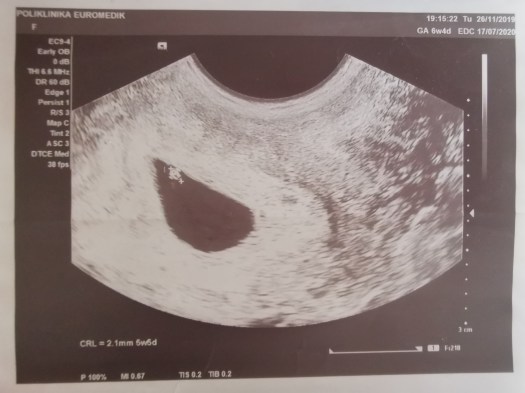

PRVI ULTRAZVUK – 26. XI 2019.

Ovo je dan nakon što sam saznala da sam trudna. Kad su mi na e-mail prethnodnog stigli rezultati da mi je beta HCG povišen (to je znak začeća), zakazali smo pregled u Euromediku i eto tebe veličine 2mm u mom stomaku. Čula sam otkucaje srca i pitala sam doktorku da li su moji, a ona je radosno odgovorila : “Ne, bebini”. Usledilo je zaprepašćenje jer si bio star samo 5 nedelja i 5 dana što se može videti na slici iznad. Žao mi je što i tata nije bio prisutan, čekao je ispred ordinacije.